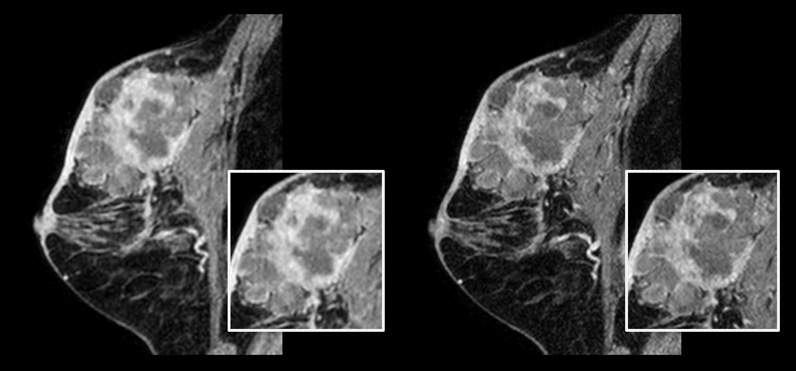

乳がんのある患者

左の画像:従来の3D mDIXON XD(等方ボクセルサイズ:1.0 mm、スキャン時間:2分22秒)

右の画像:Compressed SENSE 3D mDIXON XD(等方ボクセルサイズ:0.8 mm、スキャン時間:2分21秒)

資料提供:倉敷中央病院、岡山

乳腺の撮像においては、非常に小さい病変を識別できるよう高い空間分解能であることが重要です。そのためには、短いスキャン時間だけでなく、2D T1強調画像とT2強調画像における高い空間分解能も必要です。Compressed SENSEを使用することで高い空間分解能が得られ、より確信のある画像診断を行うことができます」

小山貴医師、博士(医学)、放射線診断医、放射線診断科主任部長、放射線センター長、倉敷中央病院